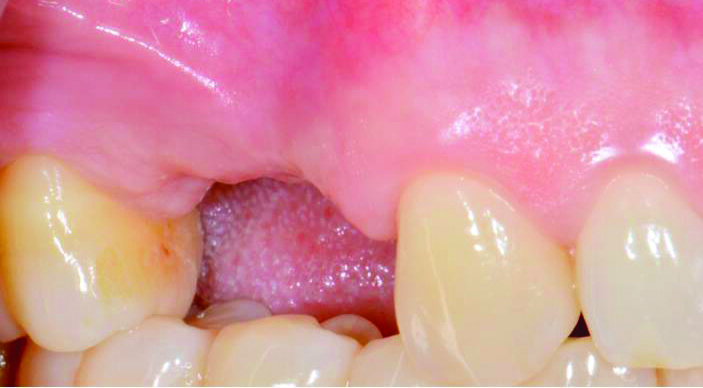

Paziente donna di 45 anni, non fumatrice, presenta alla nostra attenzione un’edentulia parziale superiore, in seguito all’estrazione di 2 elementi avvenuta 8 settimane prima (Fig. 1). L’anamnesi medica per patologie sistemiche risulta negativa. Gli indici di placca (FMPS) e sanguinamento (FMBS) presentano valori rispettivi di 16 e 12. L’esame intraorale rivela una sella edentula estesa per circa 18 mm in senso mesio-distale, dall’elemento 13 al 16 (Figg. 2, 3).

Fig. 2_Visione laterale della sella edentula in sede 14 e 15: è ben visibile la contrazione tissutale sull’aspetto vestibolare della cresta residua.